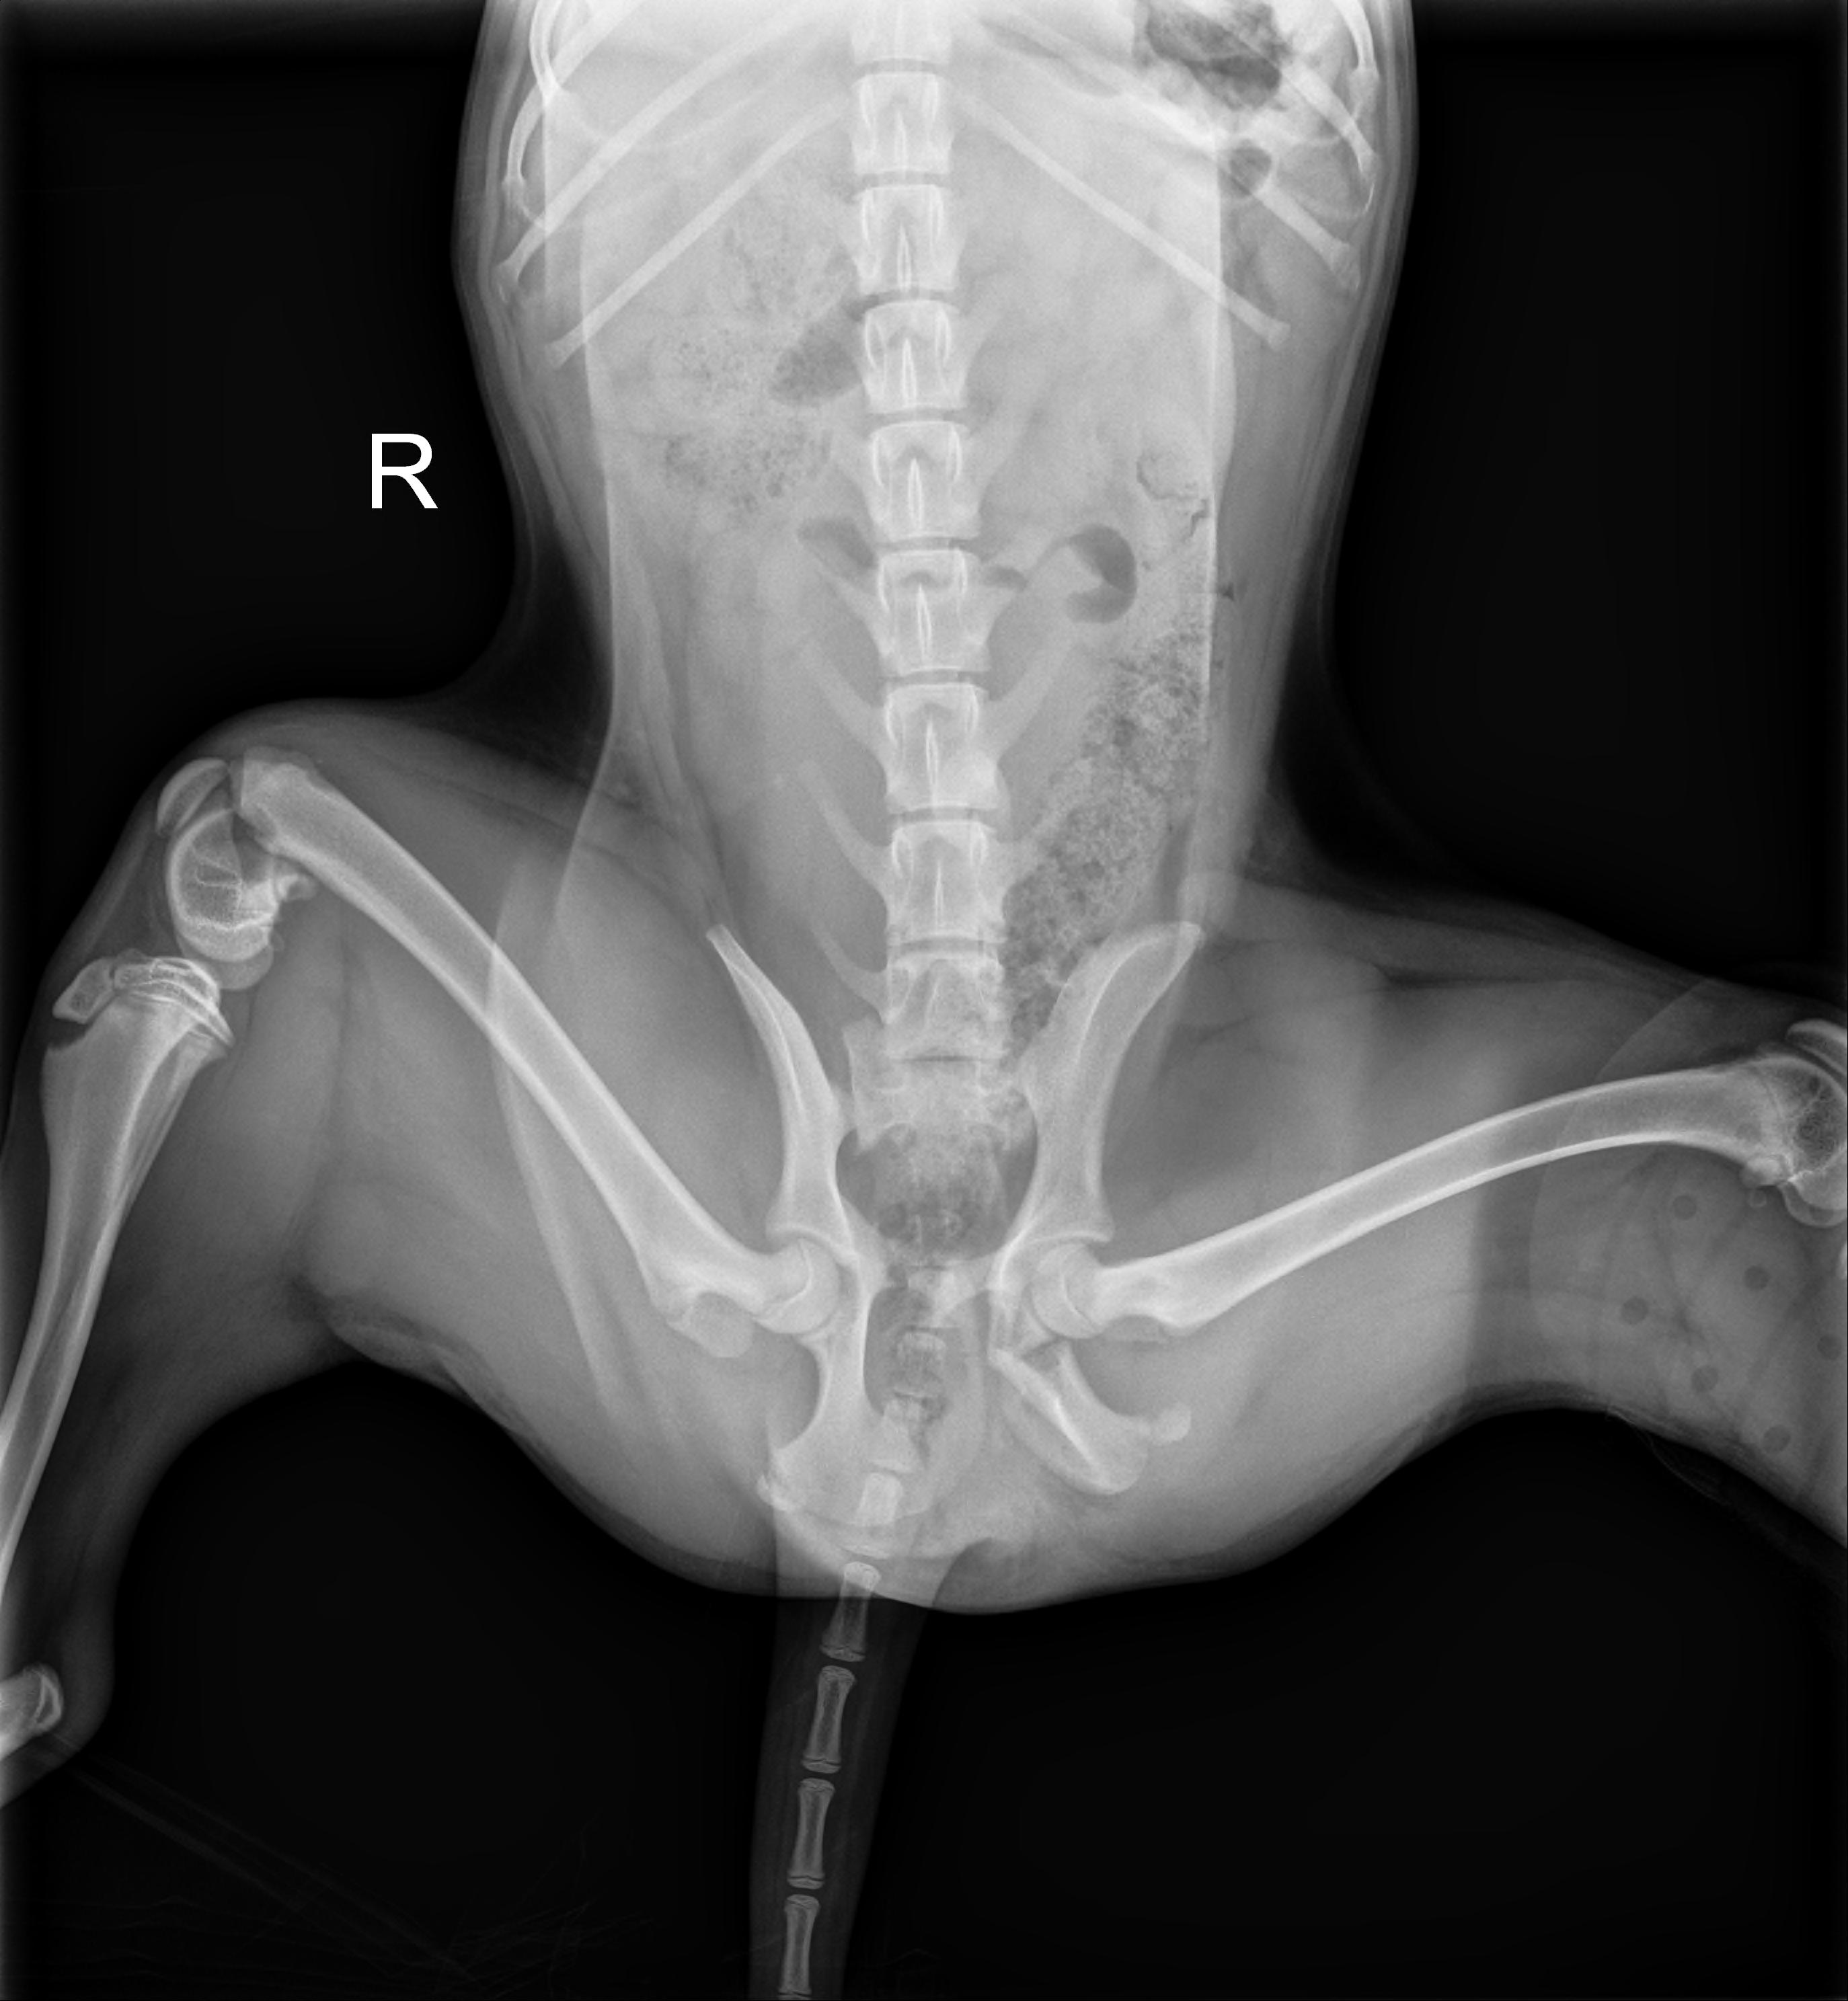

RIFF RAFF (Beagle Mix)

I am happy to report that dear Riff-Raff has done incredibly well since his surgeries.  He is now able to run around and play to his heart's content. It seems like he was going to have to wear the splint on his leg forever. Riff-Raff hated the splint, so it became a challenge to keep it intact.  For almost four weeks, he had to have a collar on to prevent him from chewing on it. Even with the collar on, he sometimes managed to get to his leg.

This vicious cycle kept each of us on our toes. The other problem was we wanted him to be able to play with some of the other pups during this time in a controlled small area.  After a short period, they would start chewing on his brace. I don't believe we have ever had to change a bandage more than we have had to change this adorable pups bandage.

The day his Surgeon finally said the Splint could be removed was the happiest day for all of us.  Riff-Raff was free of the collar and the brace in one clean sweep. He ran, play and wrestled for most of the day with all of his buddies. You would never know how broken he was from the day we got him to today.  He is an entirely different dog.   He went from not being able to stand to run around playing like a puppy.